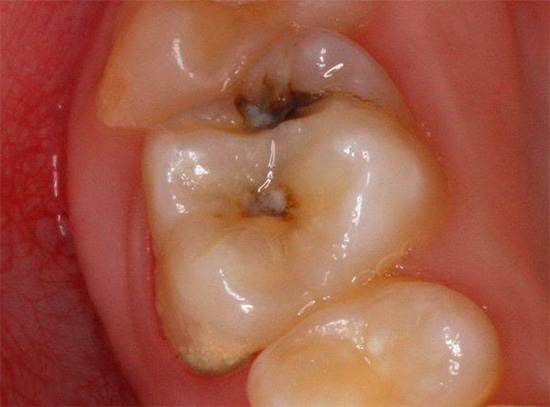

Pertanto, un marcatore di carie aumenta significativamente l'affidabilità della diagnostica della carie. Colora efficacemente le aree cariate in qualsiasi fase dello sviluppo della malattia, incluso lo stadio della macchia, mentre penetra fino a una certa profondità del tessuto interessato e aiuta il medico anche nella fase di rimozione delle aree necrotiche del dente.

Dopo il trattamento con una soluzione colorante della cavità cariata, è sufficiente che il medico pulisca i tessuti colorati con l'indicatore con un trapano e, dopo ogni rimozione, tratti le pareti della cavità con una nuova porzione del marker. Questa procedura si ripete fino a quando le pareti della cavità non smettono affatto di macchiarsi, il che indicherà la completa rimozione dei tessuti colpiti dalla carie.